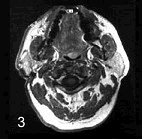

女性,55岁。右耳垂下无痛性肿块逐渐缓慢长大6年。触诊肿块界线清楚,活动,约4cm×5cm大小,表面呈结节状,中等硬度,与皮肤无黏连。

CT 检查结果如图,该病最可能的诊断是 ( )